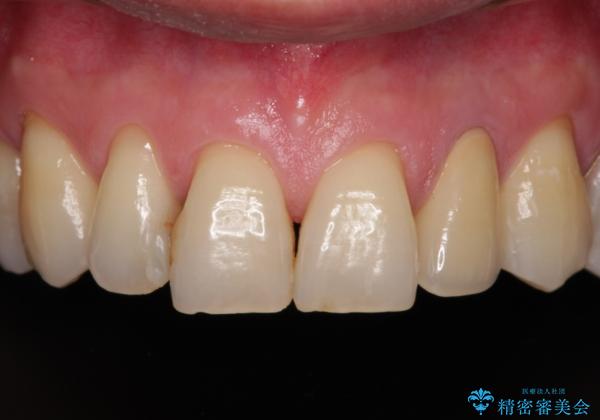

- 前歯の根管治療の際に、一時的に見た目を回復したままの状態で放置してしまったとのことで来院された患者様です。

土台の状態は良好であったため、仮歯に置き換えた上でオールセラミッククラウンにて補綴治療を行うこととしました。

見た目の改善はもちろんですが、ものが挟まらなくなったり、舌触りが良くなったりと、口腔内の状態が改善されました。